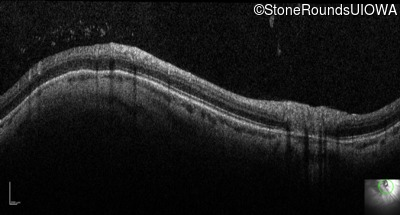

Optical Coherence Tomography - Left - 20/100

Exemplar